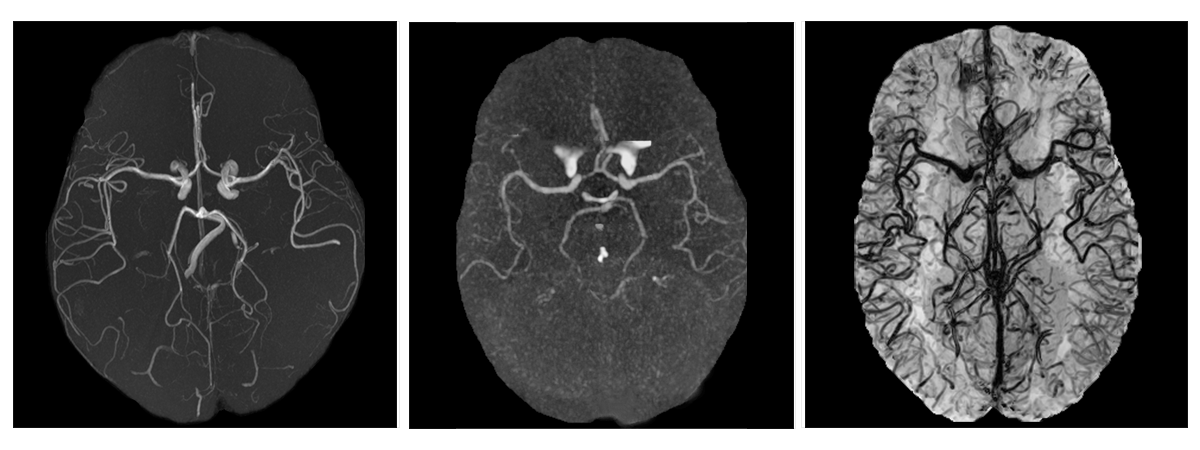

Figure 1: Maximum intensity projection (MIP) of a magnetic resonance angiography (left), MIP of a computed tomography angiography (center), and minimum intensity projection (mIP) of a magnetic resonance venography (right). All images are skull-stripped and viewed from the axial perspective.

Segmenting the cerebrovascular tree is crucial for accurately diagnosing and treating several brain-related conditions. The complex and intricate morphology of brain vessels requires the usage of multiple imaging modalities. Each modality has specific properties targeting a vessel type: angiographies focus on visualizing the arteries in the brain, while venographies primarily examine the veins. This variety of imaging modalities, combined with the different acquisition protocols and scanners utilized in clinical centers, poses challenges for automatic segmentation models, which struggle to generalize across different domains, i.e., varying centers, modalities, or vessel types (arteries or veins). When trained on a single source domain, models may become susceptible to distribution shifts, i.e., their performance may decline when transitioning from one domain to another. At the same time, developing, deploying, and maintaining a segmentation model for each domain is impractical, as collecting medical images is costly, and data annotation is laborious and demands a high level of expertise.

Figure 1 illustrates the visual disparity between a magnetic resonance angiography (MRA), a computed tomography angiography (CTA), and a magnetic resonance venography (MRV). This disparity can vary between different modalities. For example, arteries in MRA and CTA mainly differ in intensity distribution, as in the former, they stand out due to their high-intensity values, while in the latter, they blend with extracerebral tissue, making them harder to distinguish. Instead, the MRA-to-MRV domain gap also includes dissimilarities in the locations, shapes, and densities of the cerebral vasculature: although there is a correlation between the morphology of arteries and veins, the former are less numerous, occupy deeper positions within the brain tissue, and generally have larger sizes.